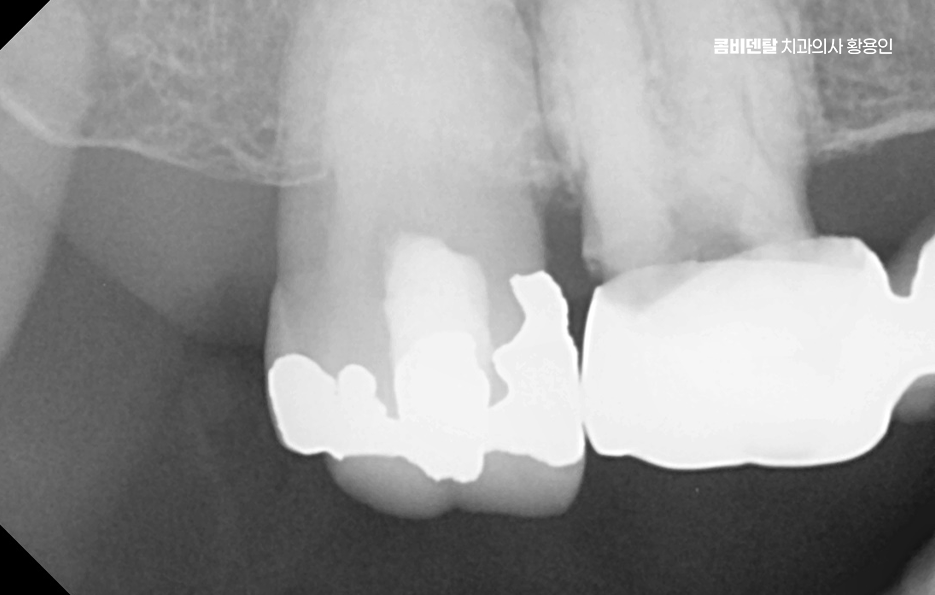

어금니가 빠지고 나서 어금니 임플란트 안하면 그 자리에 있던 치아가 받던 씹는 힘이 인접한 치아로 분산되기 때문에 그 치아들이 점점 기울거나 밀려나게 되고 결국 반대편 치아와의 맞물림도 흐트러지면서 전체 교합이 틀어지게 될 수 있어요

그뿐 아니라 맞물리는 반대편 치아는 치아가 빠진 공간 쪽으로 점점 윗니가 내려오거나 아랫니가 올라오게 되는데 이걸 정출 현상이라고 하며 결국 정출된 치아는 뿌리가 노출되고 시리고, 나중엔 치아 수명이 급격히 저하될 수 있기 때문에 어금니 하나 빠졌을 뿐인데 라고 생각하기에는 이러한 다양한 문제로 이어질 수 있는 거예요

이러한 문제를 막기 위한 효과적인 방법이 바로 임플란트 치료로 어금니 임플란트를 계획할 때는 먼저 잇몸뼈 상태를 정밀하게 확인해야 하며 3D CT 촬영을 통해 뼈의 높이와 두께, 그리고 임플란트를 심을 수 있는 공간을 세밀하게 분석해야 하며 위턱 어금니 같은 경우 상악동이라는 빈 공간이 바로 위에 있어서, 치아가 빠지고 나면 그 공간이 아래로 내려와 임플란트를 심을 자리가 부족해지는 경우가 많고 아래턱 어금니는 하치조신경이라는 중요한 신경이 지나가기 때문에, 신경을 피해서 정확한 위치와 각도로 식립하는 계획이 필요할 수 있어요